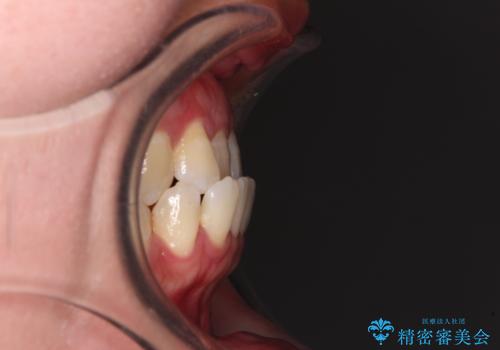

- 全顎的なクロスバイトと反対咬合を気にして来院された患者様です。

骨格的に下顎が前方位にありましたが、歯並びにより下顎が本来の位置よりも前方位に誘導される咬み合わせとなっていました。

上顎歯列および上顎骨が下顎に対して狭小であることが原因であるため、上顎の急速拡大装置を使用して上顎骨を側方に拡大することで反対咬合を改善し、ワイヤー装置で歯列を整えることとしました。